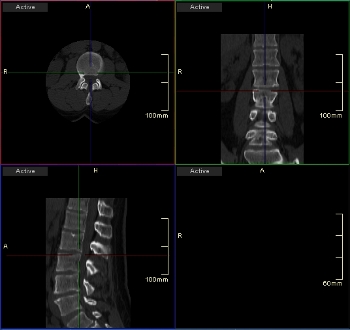

Η προεπιλεγμένη διάταξη MPR αποτελείται από τρία χρωματικά κωδικοποιημένα παράθυρα που εμφανίζουν εγκάρσια, στεφανιαία και οβελιαία επίπεδα. Κάθε ένα από αυτά τα παράθυρα περιέχει δύο τεμνόμενες γραμμές εντοπισμού που αντιπροσωπεύουν τα επίπεδα που είναι ορατά στα δύο άλλα παράθυρα. Οι γραμμές εντοπισμού είναι επίσης χρωματικά κωδικοποιημένες για να αντιστοιχούν στις προβολές που αντιπροσωπεύουν.